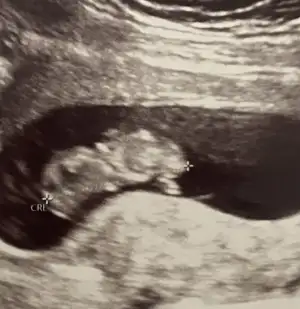

bende tahmin alabilirmiyim